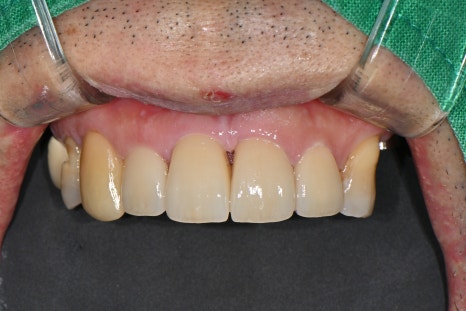

🖼️ After lip and gum recovery / Front view after the fixation device on the front tooth was removed

Front view photo after stitch removal

🖼️ Final front tooth prosthesis photo

Front view after the final prosthesis was placed

After root canal treatment was completed, the front tooth was finished with an esthetic prosthesis in collaboration with our in-house dental technician.

It was made in a natural color and shape that was almost indistinguishable from the existing teeth,

and because it did not look noticeable even when smiling, the patient was very satisfied.